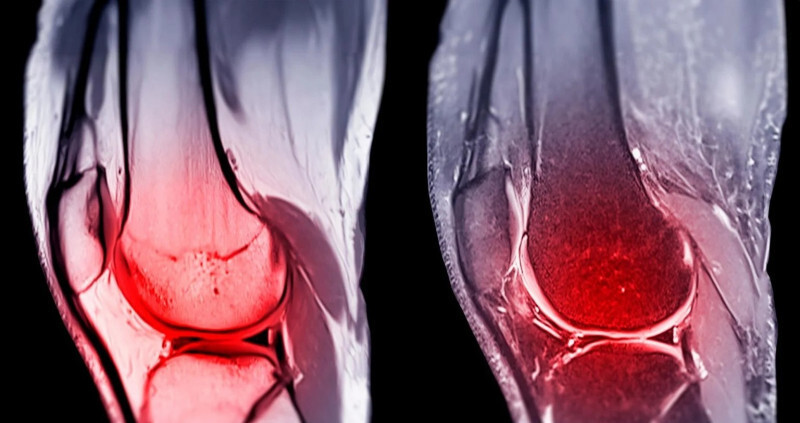

〔編譯陳成良/綜合報導〕據科技媒體《SciTechDaily》報導,史丹福醫學院(Stanford Medicine)研究團隊在頂尖期刊《科學》(Science)發表重大發現。科學家識別出 1種隨年齡增長而劇增的特定蛋白質,透過阻斷該蛋白,在小鼠實驗中成功促進軟骨再生。這項技術不依賴幹細胞,而是透過「重編譯」現有細胞使其恢復年輕狀態,未來有望讓患者免於接受人工關節置換手術。

退化性關節炎影響全球數億人,每年產生高達650億美元(約新台幣2兆391億元)的醫療支出。史丹福團隊發現,一種名為「15-PGDH」的蛋白質被歸類為「衰老酶」(Gerozyme),會隨老化而增加並導致組織衰退。布勞(Helen Blau)教授指出,當阻斷老化小鼠體內的「15-PGDH」時,原本受損的軟骨顯現劇烈再生,且生成的是具備高功能的「透明軟骨」。

除了自然老化,膝蓋外傷也是引發關節炎的主因。研究針對類似人類「前十字韌帶」(ACL)撕裂的受傷小鼠進行測試,發現受傷後每週注射 2次阻斷劑,能顯著降低轉化為退化性關節炎的機率。未治療的對照組小鼠在 4週內即出現嚴重退化,且體內「15-PGDH」含量是正常組的2倍,證實該蛋白是驅動病變的關鍵。

這項技術在離體的人體膝蓋組織測試中亦顯現再生信號。然而研究人員強調,目前相關研究仍屬「前臨床階段」,療法的長期安全性、再生軟骨的承重能力,以及對重度關節炎患者的適用性,仍需後續人體臨床試驗進一步確認。